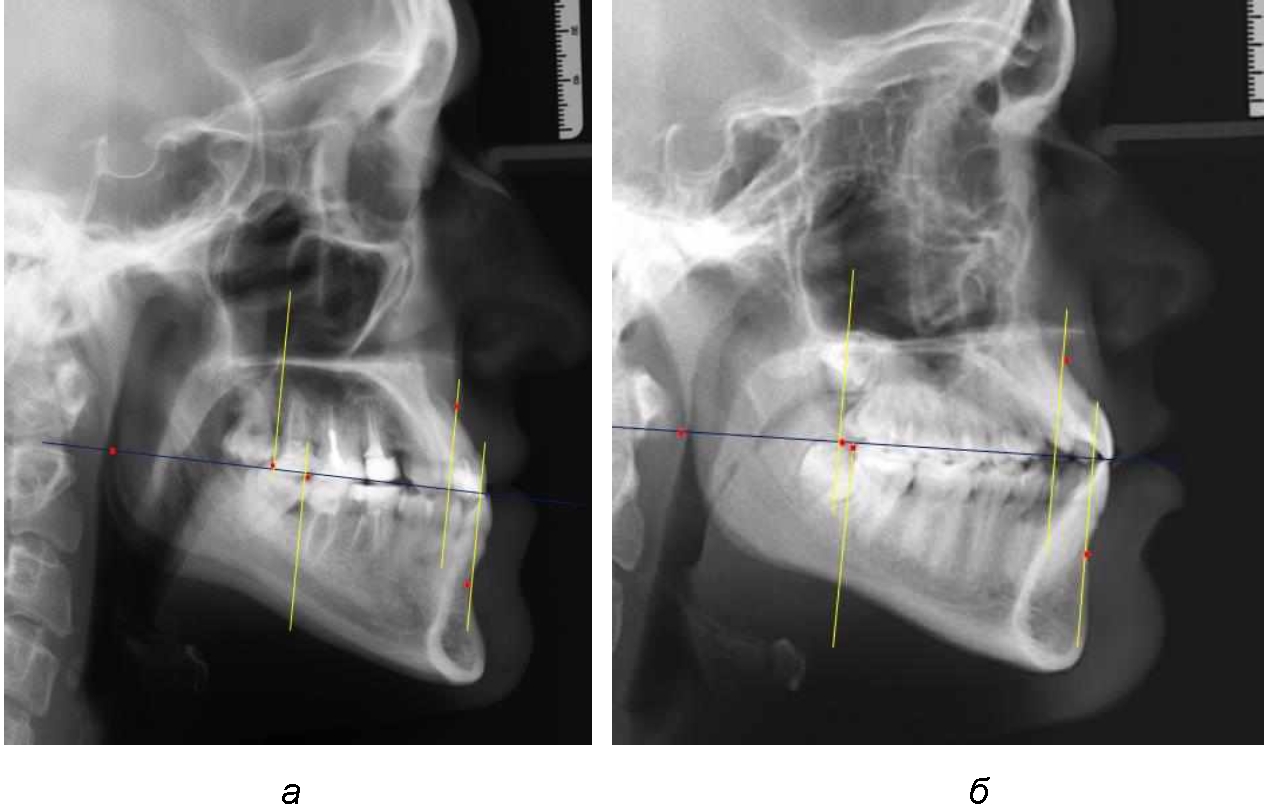

При анализе рентгенограмм, было отмечено, что на 26 снимках из 58 [(44,83 ± 6,53) %] отмечалась нормопозиция верхней челюсти. При этом средняя величина лицевого угла (ANSe) составила (85,04 ± 0,56)°, и пациенты были отнесены к 1-й группе 1-й подгруппе. Антепозиция верхней челюсти была отмечена на 20 те-лерентгенограммах [(34,483 ± 6,24) %], при этом величина лицевого угла составляла (89,12 ± 0,62)°. Ретропозиция была отмечена на 12 рентгенограммах [(20,69 ± 5,32) %], а средняя величина лицевого угла составляла (80,21 ± 0,48)°.

При всех вариантах положения верхней челюсти, было отмечено, что альвеолярно-денталь-ные размеры верхних зубо-челюстных дуг были близки по значению к аналогичным размерам нижней челюсти и разница в размерах не превышала 1,0–1,5 мм, а средняя величина различия показателей составляла (1,07 ± 0,54) мм.

Расстояние от конструируемой точки окклюзионной плоскости на ветви челюсти («rmРOcP») до апикальных точек Downs на обеих челюстях также коррелировало между собой, и средняя величина различия показателей составляла (1,23 ± 0,69) мм. Проекция нижней апикальной точки на окклюзионную линию, как правило, располагалась несколько кпереди проекции верхней апикальной точки, на величину около 1 мм, что соответствовало оптимальным данным Wits-анализа.

Аналогичное расстояние было отмечено и при расположении дистальных окклюзионных точек верхней и нижней челюсти (рис. 2).

Рис. 2. Положение апикальных точек и челюстей при нормопозиции (а), антепозиции (б) и ретропозиции (в) верхней челюсти